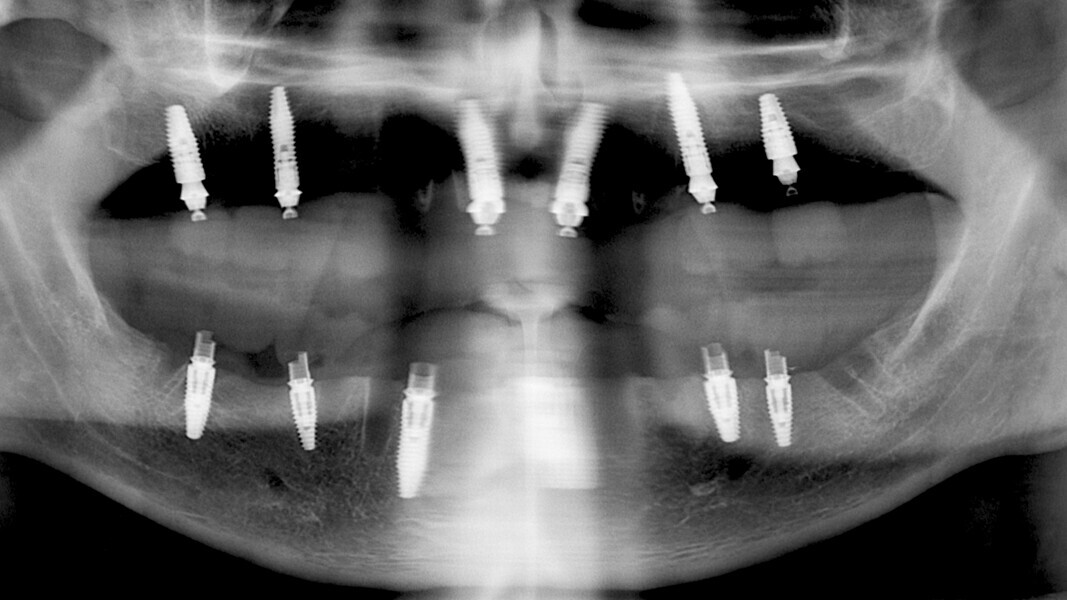

The fully digital Pro Arch protocol